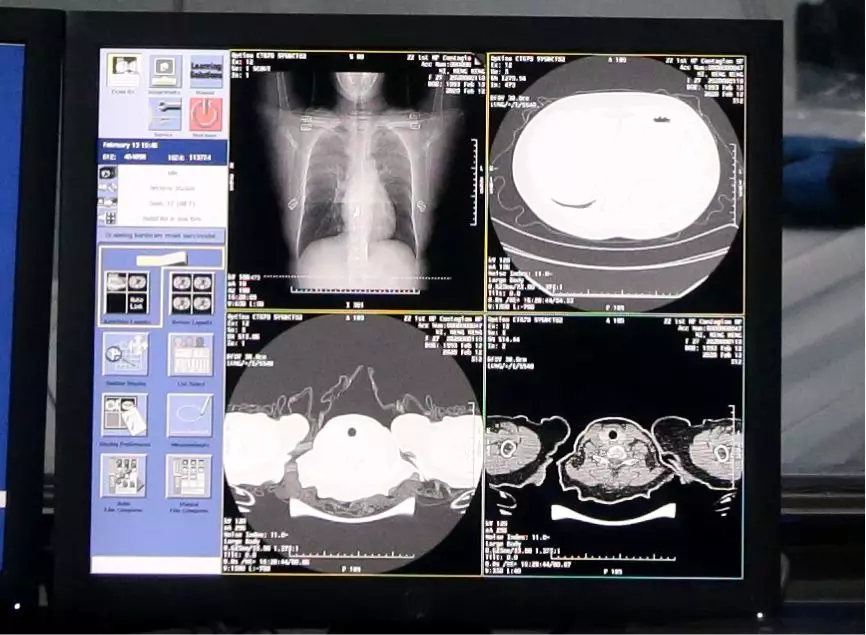

医护人员使用AI识别新冠肺炎病例CT影像

AI 正在成为疫情防控战的“新兵种”。一位新冠肺炎病人的 CT 影像大概在 300 张左右,医生对一个病例的 CT 影像肉眼分析耗时大约为 5-15 分钟,这给医生临床诊断带来巨大压力。

阿里云和达摩院医疗 AI 团队联合研发“新冠病毒 AI 辅诊助手”,它可以在 20 秒内准确地对新冠疑似案例 CT 影像做出判读,从而自动判断患者新冠肺炎概率,识别准确率达 96%,大大提高诊断效率,减轻医生压力。此外,AI 还能直接算出病灶部位的占比比例,进而量化病症的轻重程度,大幅提升临床诊断效率。